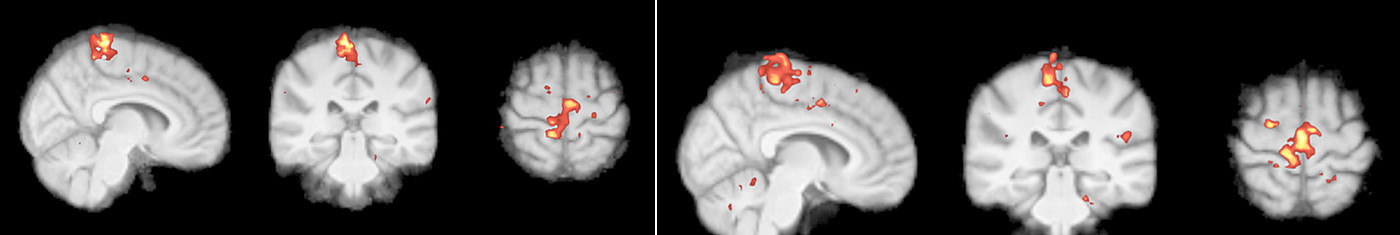

Funktionelles und metabolisches MRT:

Es ist bekannt, dass chronische Schmerzen zu funktionellen und strukturellen Änderungen im Gehirn führen. In diesem Projekt untersuchen wir den Einfluss der Rückenmarksstimulation auf diesen Prozess.